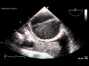

large atrial tumor: filling the whole right atrium.apical view